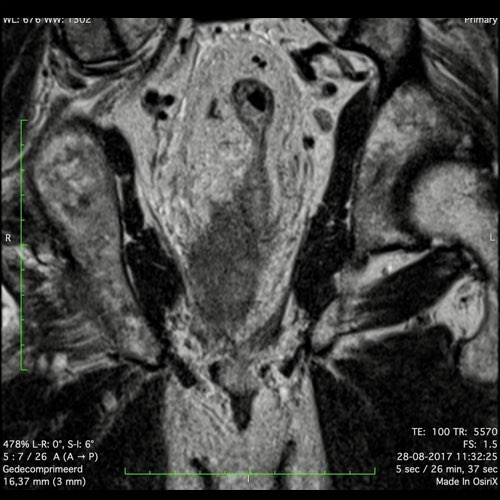

Hình ảnh

Các hình ảnh được cung cấp cho thấy ung thư biểu mô tế bào nhẫn với tình trạng dày lan tỏa thành trực tràng, hình ảnh bia bắn điển hình, và sự xâm lấn mỡ mạc treo trực tràng.